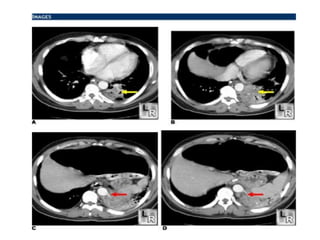

Figure 25a. PE cấp ở bn nam 59 tuổi.

(a) CT scan (window width = 400 HU, window level = 40 HU) cho thấy huyết

khối ở đm liên thùy (P) (mũi tên).

Figure 25b. PE cấp ở bn nam 59 tuổi.

(b) CT scan (window width = 552 HU, window level = 276 HU) cho thấy PE cấp

ở nhánh trong của đm thùy giữa (P). (mũi tên) dấu hiệu này không thấy trên

hình 25a.

Figure 25c. PE cấp ở bn nam 59 tuổi.

(c) CT scan (window width = 700 HU, window level = 100 HU) cho thấy

thrombus ở đm liên thùy (P) và nhánh trong của đm thùy giữa (P).

- Hình 25 cho thấy ở các cửa sổ khác nhau có hiệu quả phát hiện huyết khối

khác

nhau.